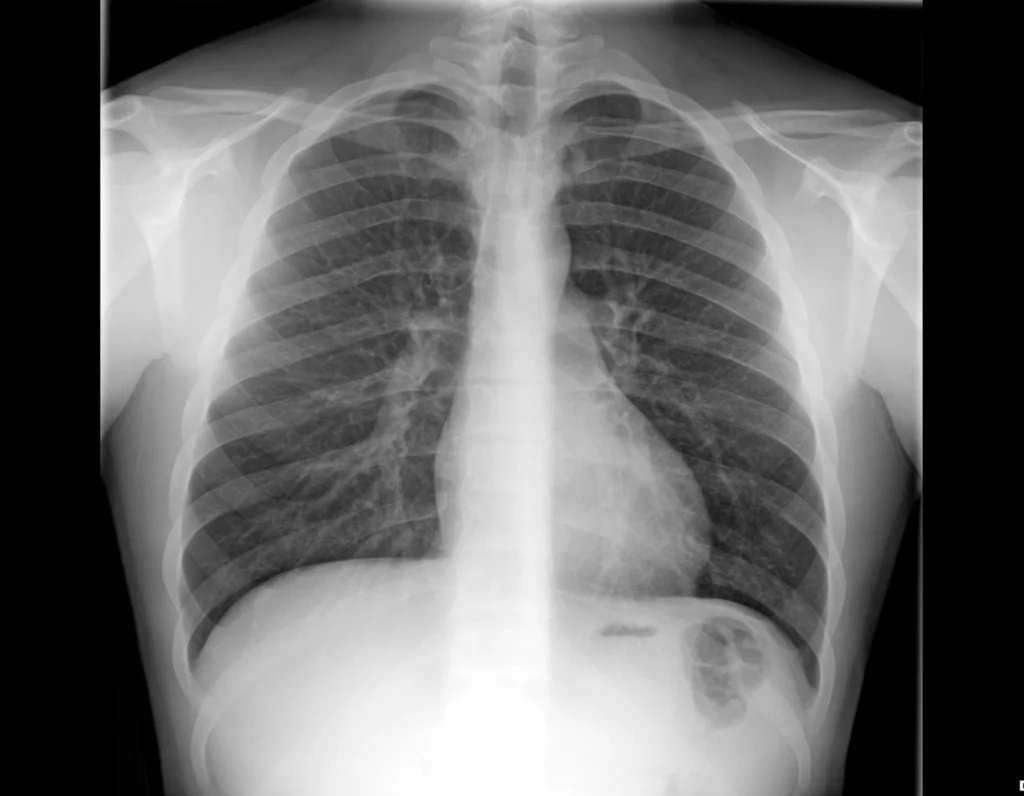

Radiografía simple de tórax utilizada como ejemplo docente para ilustrar la apariencia de la densidad aérea.

Género:

Masculino

Los campos pulmonares se observan ampliamente radiolúcidos, correspondientes a la presencia de aire, que constituye la densidad de menor atenuación en la radiografía convencional.

El aire permite el paso de la mayor parte de los rayos X y, por lo tanto, se representa como áreas oscuras o negras en la imagen radiográfica.

En el tórax, la presencia de aire en los pulmones actúa como contraste natural y facilita la visualización de las estructuras mediastínicas.